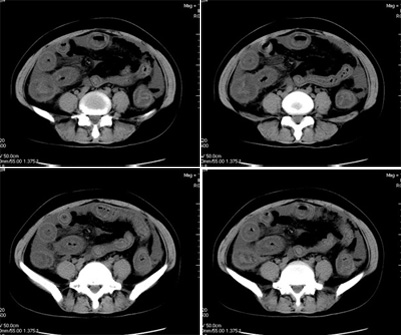

女,42岁,既往体健,近一月来无明显诱因下出现恶心呕吐,同时出现腹泻,否认有结核病,糖尿病史,入院后检查,胸片未见明显异常,ppd阴性,肝转氨酶正常,腹水检查,在漏出液与渗出液之间,胃镜慢性浅表性胃炎,盆腔b超.盆腔积液.

平扫一部分图片

真是少见!至少本人从未见过!整个消化道除了胃壁以外整套小肠及结肠肠壁均不同程度增厚水肿,肠壁间未见积气,亦未见明显的血运障碍(肠细膜上动静脉均显示很好)。盆腹腔积液。

真是少见!至少本人从未见过!整个消化道除了胃壁以外整套小肠及结肠肠壁均不同程度增厚水肿,增强明显分层[粘膜层及浆膜层明显强化,粘膜下层强化轻]。结合病史考虑肠道缺血改变[病因待查--血管炎,结缔组织疾病等]

真是少见!至少本人从未见过!整个消化道除了胃壁以外整套小肠及结肠肠壁均不同程度环形增厚,肠壁密度均匀呈“晕圈”样改变,粘膜下层低密度,粘膜层和外层为相对高密度。增强强化不明显。结合病史考虑肠道急性缺血改变。腹水。形成原因肠系膜动脉栓塞、还是静脉血栓形成看不懂。

真是少见!我也从未见过!整个消化道除了胃壁以外整套小肠及结肠肠壁均不同程度同心圆样增厚,肠壁密度均匀呈“晕圈”样改变,粘膜下层低密度,粘膜层和外层为相对高密度;增强强化不明显。腹腔各个间隙内液性密度积液影,结合病史考虑:肠道慢性中毒性改变(药物性中毒可能性大)。腹水形成原因?

本例ct表现是肠道的整体性充血、水肿,以结肠特别是横结肠、升结肠、盲肠为显著,横结肠一眼粗略看过去,极似极度水肿之胰腺。回肠末段亦呈明显近似结肠改变,小肠则以充血为主,水肿相对轻微。诸段肠管无明显如溃疡、出血等局部损害,重度腹水。肝脏体积变小,肝裂增宽,以肝圆韧带为明显。肝脏各部比例尚正常,无局部外突或内凹,密度均匀一致。胆囊增大,所给图片及楼主已经仔细观察过,肝段下腔静脉肠系膜静脉均正常。